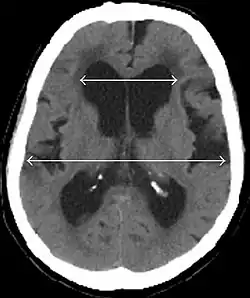

Normal pressure hydrocephalus (NPH), also called malresorptive hydrocephalus, is a form of communicating hydrocephalus in which excess cerebrospinal fluid (CSF) builds up in the ventricles, leading to normal or slightly elevated cerebrospinal fluid pressure. The fluid build-up causes the ventricles to enlarge and the pressure inside the head to increase, compressing surrounding brain tissue and leading to neurological complications. Although the cause of idiopathic (also referred to as primary) NPH remains unclear, it has been associated with various co-morbidities including hypertension, diabetes mellitus, Alzheimer's disease, and hyperlipidemia.[1][2][3] Causes of secondary NPH include trauma, hemorrhage, or infection.[4] The disease presents in a classic triad of symptoms, which are memory impairment, urinary frequency, and balance problems/gait deviations (note: use of this triad as the diagnostic method is obsolete; the triad symptoms appear at a relatively late stage, and each of the three can be caused by a number of other conditions[5][6]). The disease was first described by Salomón Hakim and Raymond Adams in 1965.[7]

Every day, the body makes roughly 600–700 ml of CSF, and about the same amount is reabsorbed into the bloodstream. Hydrocephalus is caused by an imbalance between the amount of fluid produced and its absorption rate. Enlarged ventricles put increased pressure on the adjacent cortical tissue and cause myriad effects in the patient, including distortion of the fibers in the corona radiata. This leads to an increase in intracranial pressure (ICP). The ICP gradually falls but remains slightly elevated, and the CSF pressure reaches a high normal level of 15 to 20 cm H2O. Measurements of ICP, therefore, are not usually elevated. Because of this, patients do not exhibit the classic signs that accompany increased intracranial pressure such as headache, nausea, vomiting, or altered consciousness, although some studies have shown pressure elevations to occur intermittently.[12][13]

- Imaging from magnetic resonance imaging (MRI) or computed tomography (CT) is needed to demonstrate enlarged ventricles and no macroscopic obstruction to cerebrospinal fluid flow. Imaging should show an enlargement to at least one of the temporal horns of lateral ventricles, and impingement against the falx cerebri resulting in a callosal angle ≤ 90° on the coronal view, showing evidence of altered brain water content, or normal active flow (which is referred to as "flow void") at the cerebral aqueduct and fourth ventricle.

MRI scans are the preferred imaging. The distinction between normal and enlarged ventricular size by cerebral atrophy is difficult to ascertain. Up to 80% of cases are unrecognized and untreated due to difficulty of diagnosis.[22] Imaging should also reveal the absence of any cerebral mass lesions or any signs of obstructions. Although all patients with NPH have enlarged ventricles, not all elderly patients with enlarged ventricles have primary NPH. Cerebral atrophy can cause enlarged ventricles, as well, and is referred to as hydrocephalus ex vacuo. For these reasons it's utmost important to note that Evan's index although commonly used in imaging is not very specific for NPH. One recent systematic review and meta-analysis suggests that callosal angle has high diagnostic performance and is commonly used together with Evan's index.[23]